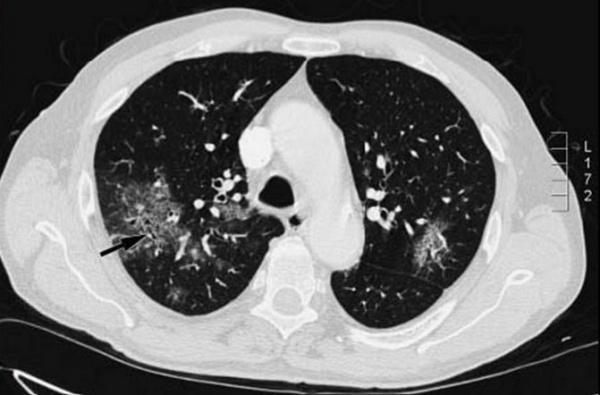

Крайне скудная аускультативная симптоматика сочетается с выраженной дыхательной недостаточностью: одышка, артериальная гипоксемия, респираторный алкалоз. При рентгенологическом исследовании легких обнаруживают облаковидную, туманную, по типу снежной бури, билатеральную инфильтрацию, распространяющуюся от корней легких к периферии. Такие изменения (билатеральные интерстициальные) являются специфичными.

Часто подобные инфильтративные изменения в легких удается выявить только при компьютерной томографии. Возможно атипичное проявление пневмонии (не является редкостью у иммунокомпрометированных больных) в виде локальной, очаговой инфильтрации, присутствия полостей. Появление жидкости в плевральных полостях не специфично для пневмоцистной пневмонии и определяется крайне редко при моноинфекции.

На рентгенограммах и КТ легких в типичных случаях определяется облаковидное понижение прозрачности легочных полей, получившее название «хлопьев снега» или «ватного легкого». Иногда рентгенологические изменения отсутствуют или имеют атипичную картину. С помощью ФВД обнаруживаются признаки дыхательной недостаточности по рестриктивному типу; исследование газового состава крови свидетельствует о гипоксемии.

- Рентгенологические. В начальной стадии пневмоцистной пневмонии на рентгенограммах легких выявляются инфильтраты, похожие на очертания крыльев бабочки. В разгаре инфекции заметны двусторонние симметричные очаги уплотнения, чередующиеся с участками вздутия («ватное» легкое). На КТ грудной клетки обнаруживаются участки инфильтрации по типу «матового стекла».